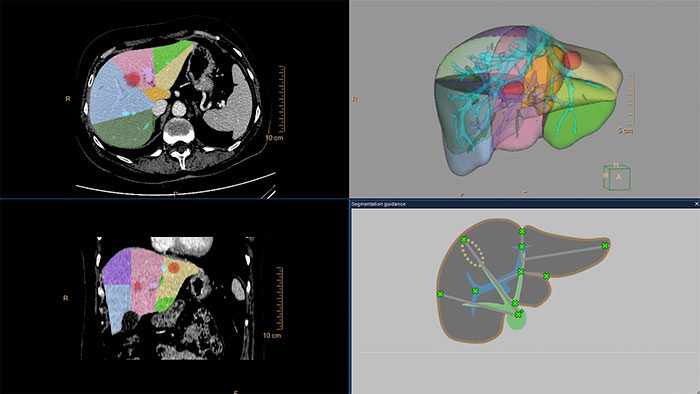

Liver Analysis

CT Liver Analysis

Advanced Liver segmentation

Automatically identifies, segments and quantifies the liver from the portal venous phase of a tri-phase liver scan and classifies the hepatic and portal veins.

Benefits

• Semi-automatic segmentation methods to segment the liver (i.e. Couinaud) and provides tools to analyze and quantify the whole liver, liver segments and user-defined regions of interest.

• Enables virtual hepatectomy, providing volumetric estimates of resected and residual liver segments.

• Results from CT Liver Analysis can be loaded into MMTT and vice-versa.

• Segmentations of the whole liver, liver segments, vasculature and findings can be exported as RT Structures.